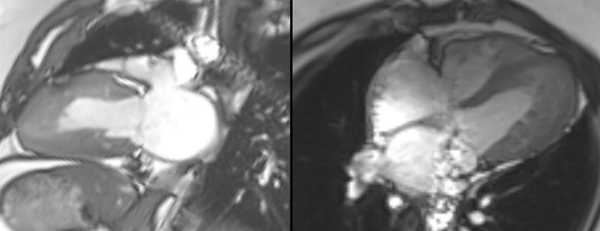

Non-Ischemic Cardiomyopathy

A lecture describing the role of CMR in the various non-ischemic cardiomyopathies